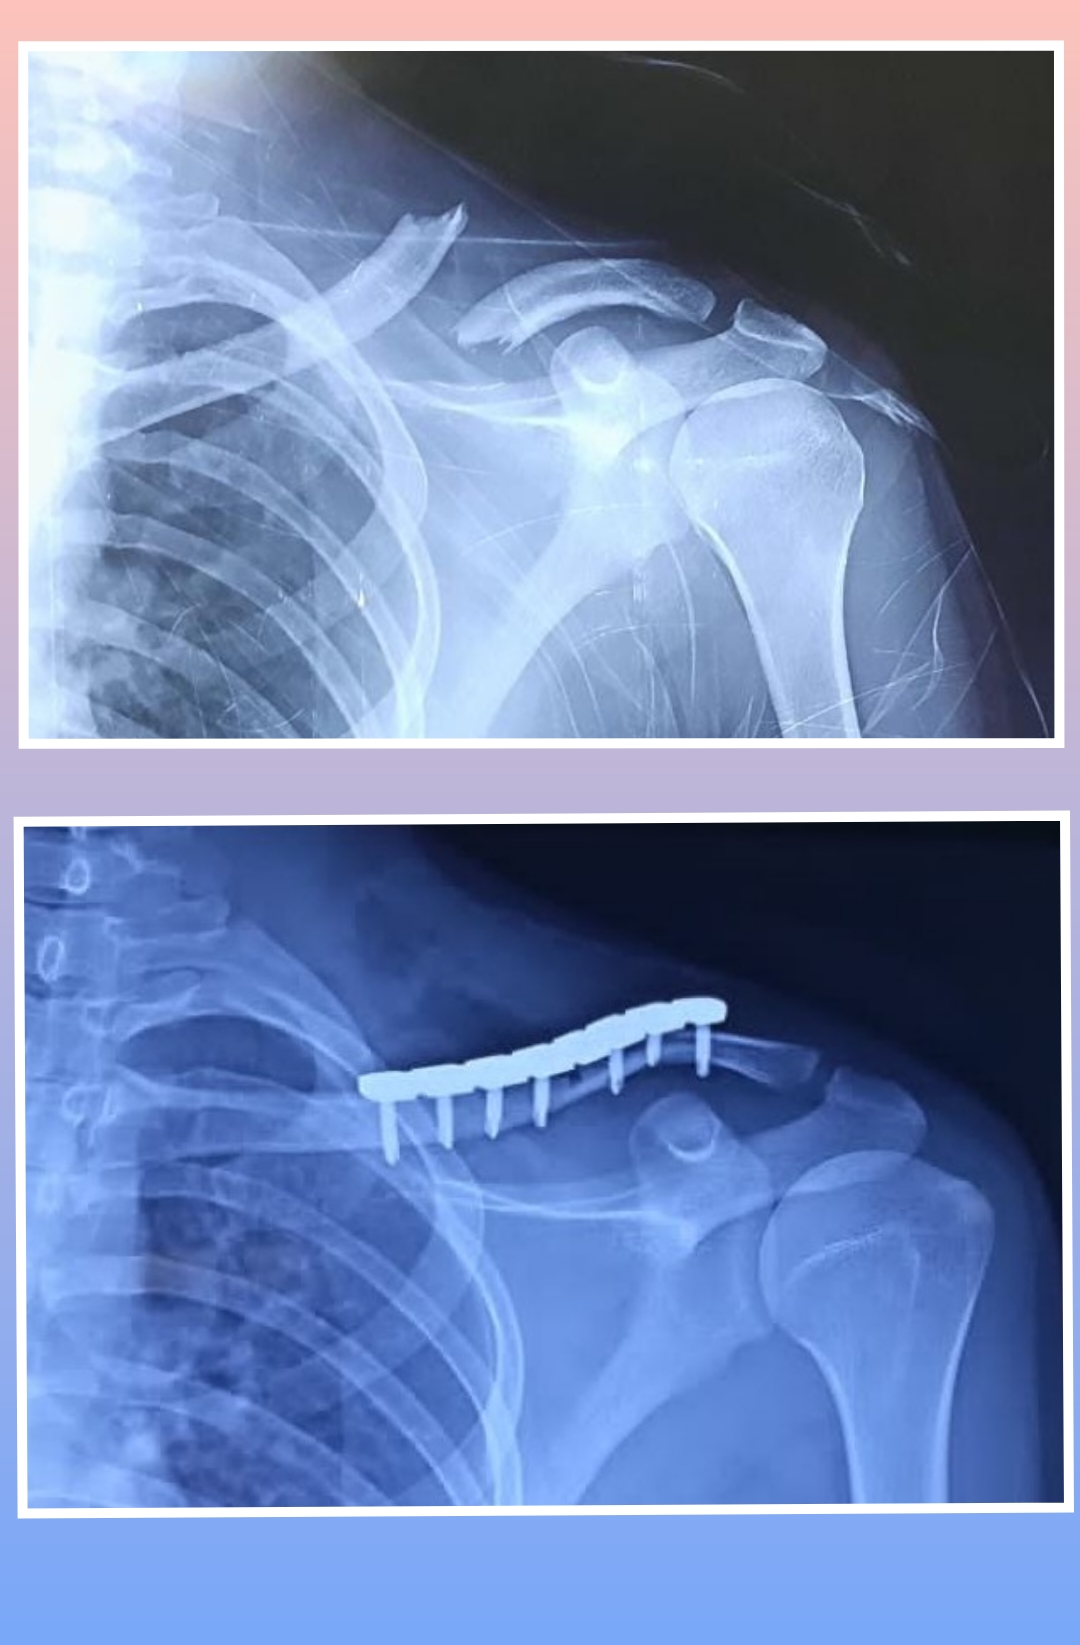

X-ray

Surgeries